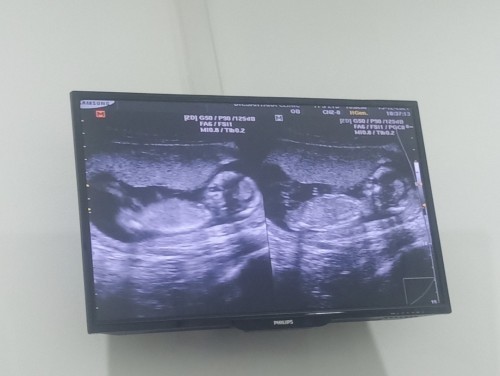

แม่บ้านนี้13w3dคะกำหนดคลอด24มิถุนาคะแม่ก็ยังไม่รุ้เพศน้องเหมือนกันคะลุงหมอบอกน้องยังตัวเล็กอยู่เลยยังดูไม่ออกรอนัดหน้าคะลุ้นอยู่คะว่าจะได้ชายหรือหญิงส่วนตัวอยากได้ลูกสาวแต่พ่อเขาอยากได้ลูกชาย😊😊

ดูแบบนี้ไม่รู้หรอกค่ะ เค้าต้องส่องไปตรงหว่างขา ถ้าให้ชัดต้อง 18w ขึ้นไป หรือถ้าให้ชัวร์ต้องครวจ Nifty ค่ะ

ถาพที่แม่ให้มาไม่ใช่ตำแหน่งที่จะดูเพศจ้า ดูไม่ออกค่ะ เพราะหมอถ่ายมาด้านข้างน้องจ้า